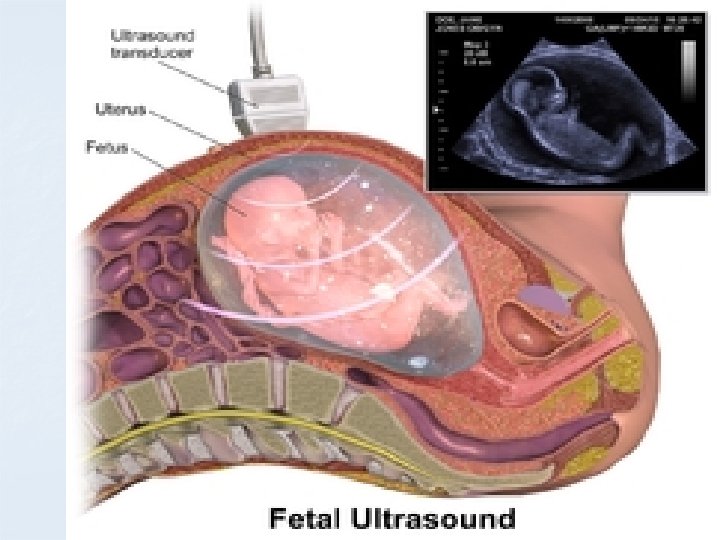

Value &Benefits n n n Noninvasive No ionizing radiation Clear picture of soft tissues Monitoring of pregnant women Guiding minimally invasive procedures

Ultrasound is energy and is absorbed by tissue, causing heating 2 D ultrasound has been used to image the foetus for about 50 years. It is thought to be completely safe and does not cause significant heating 4 D ultrasound is new, requires more energy and therefore generates more heating. We think it is safe.